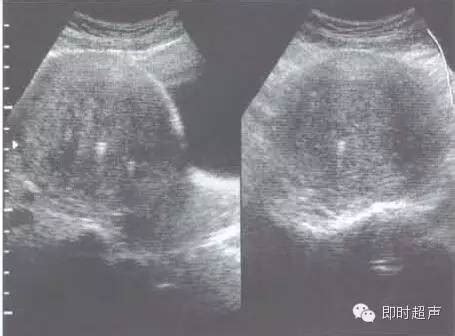

子宫腺肌症弥散性增生,直接会导致子宫的内环境不好,从而会影响患者朋友的受孕。子宫腺肌病的患者有一部分是会怀不上孕的,但有一部分有一部分怀孕后有可能出现流产及早产的现象。所以,无论为了自身还是说家庭,子宫腺肌病还是应该早日抓紧时间治疗。